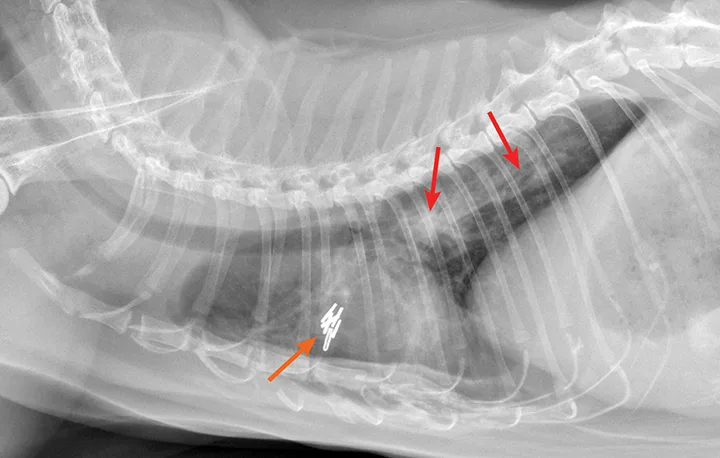

Radiographic evaluation is variable. Classic cranioventral distribution is less common in cats (Figure 3). A bronchial pattern is most common; however, bronchointerstitial, alveolar, and more structured pseudonodular patterns can occur.6,8 Occasionally, pulmonary abscesses may be appreciated and resemble pulmonary neoplasia (Figure 4).

FIGURE 4

Radiograph of pulmonary abscessation. The pulmonary nodules (arrows) could be mistaken for pulmonary neoplasia. The margins of these nodules are slightly less well demarcated than in neoplasia. Improvement was achieved with antibiotic therapy.